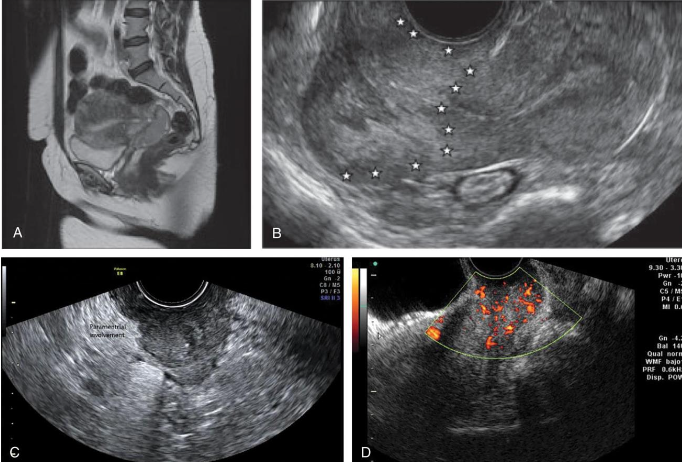

Benign disease

Diffuse or focal

Global infiltration of endometrium

Sonographically presents as bulky enlarged uterus without focal mass

Adenomyosis is ectopic occurrence of endometrial tissue within myometrium; more common in

posterior aspect

The tissue penetration usually reaches a depth of at least 2.5 mm from the basal layer of the

endometrium.

Adenomyosis may arise from multiple pregnancies and deliveries with subsequent uterine shrinking.

Elevated estrogen levels may also promote the growth of myometrial islands of endometrial tissue.

Adenomyosis is often classified into diffuse and focal forms. The more common form is diffuse

adenomyosis.

It represents a reactive hypertrophy of the myometrial muscle, which produces uterine enlargement

but usually not to the extent seen with leiomyomas.

Focal adenomyosis is sometimes called adenomyoma, referring to isolated implants that typically

cause reactive hypertrophy of the surrounding myometrium and produce diffuse uterine enlargement.

Less common than the diffuse form, focal adenomyosis (adenomyoma) lacks a hypoechoic border that

is seen with fibroids, not endometriosis. Adenomyosis can be appropriately managed with hormone

therapy.

Patients with adenomyosis are often multiparous and older than patients with endometriosis.

The patient presents with heavy, painful abnormal menses, and on physical examination, the uterus is

found to range from normal to three times normal size and is globular in contour, boggy, and

somewhat tender.

Sonographically, diagnosis may be difficult.

Most common presentation of extensive adenomyosis is:

➢ Diffuse uterine enlargement

➢ Thickening of posterior myometrium

➢ Indistinct border between endometrium and myometrium (involved area being slightly more

anechoic than normal myometrium)

Has been described as Swiss cheese or honeycomb pattern

Calcifications resulting from prior instrumentation are seen along inner myometrium and cervix.

Doppler studies have also proven helpful in differentiating uterine pathology, as color flow studies of

uterine masses show that myomas and sarcomas typically demonstrate a feeding artery, but

adenomyosis rarely demonstrates feeding arteries.

Adenomyosis is not always reliably diagnosed by ultrasonography, and

caution is advised because these findings are similar in appearance to

uterine myomas, muscular hypertrophy, myometrial contractions,

endometritis, endometrial carcinoma, and the presence of increased

endometrial secretions.

The presence of myomas has been shown to limit the ability to diagnose

the severity of adenomyosis.

Although not reliably diagnosed by ultrasonography, adenomyosis is well

characterized by MRI, which currently is thought by many to be the

best technique for the presurgical diagnosis of adenomyosis.